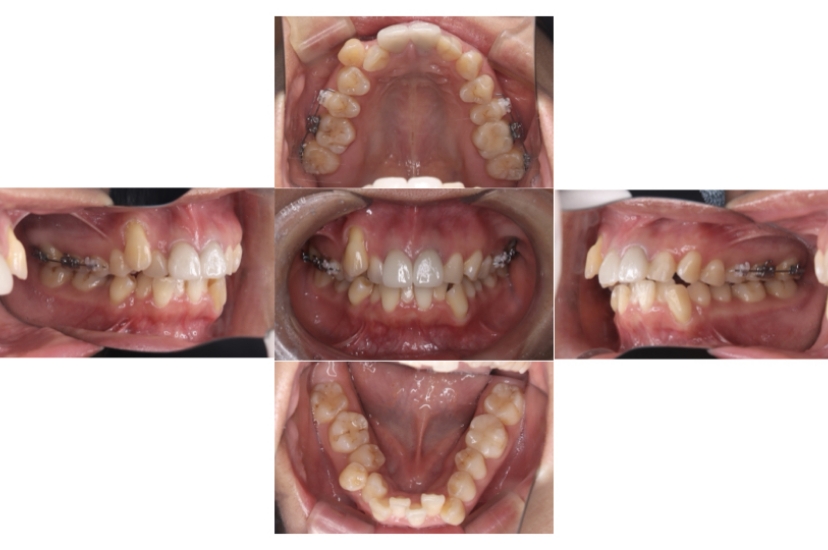

BEFORE

治療経過

AFTER

上下顎叢生(上下の前歯のガタガタ)のケースです。

装置はラビアル(上下表側)で、上下顎の小臼歯を4本抜歯を行っています。抜歯したスペースを使って、上下の前歯の後方移動と叢生(ガタガタ)の改善を行っています。

主訴 歯並びが悪く、舌を噛んでしまうのを治したい。

年齢・性別 27歳 男性

お住まいの地域 東京都大田区

治療方針 抜歯スペースを利用して上下前歯の叢生(ガタガタ)の改善

抜歯部位 上下顎左右第一小臼歯

使用装置 ラビアル(上下表側)、顎間ゴム

治療期間 3年1か月

治療回数 30回